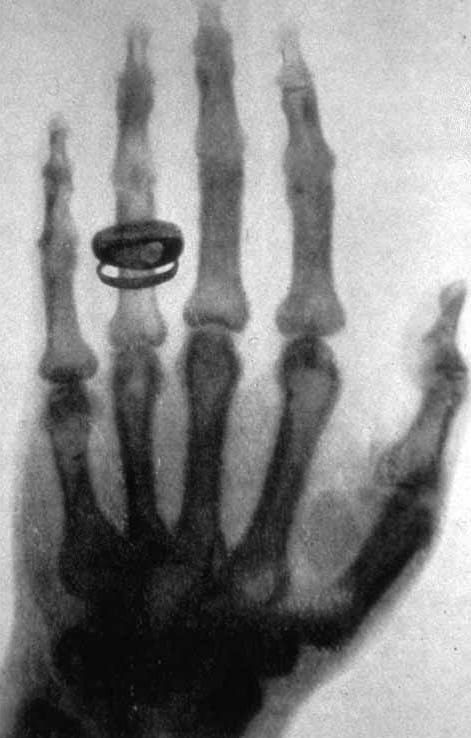

A few weeks later, Röntgen took the first X-ray picture of a human body. It showed the bones inside his wife's hand, along with her wedding ring. When she saw the image, she said, "I have seen my death." People had never looked inside a living body before.

X-rays work because different materials block them by different amounts. Soft things like skin and muscle let most X-rays pass through. Hard things like bone and metal block them. When an X-ray machine shoots rays at your arm and a detector catches them on the other side, bones show up as bright white shapes and soft tissue looks gray. A broken bone shows up as a clear crack in the white.